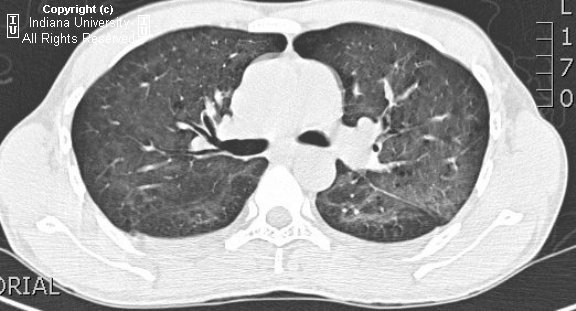

PCP pneumonia

• CXR - usually normal; may see subtle groundglass opacities

• HRCT

• Diffuse, symmetric ground-glass opacities are the dominant finding. There may be sparing of the subpleural lung in ~40% of the cases.

• Thin walled cysts in the same distribution as the ground-glass opacities may be seen sometimes. These predispose the patient to pneumothorax.

• Adenopathy and pleural effusions are rare. Consider other diagnoses in this case.